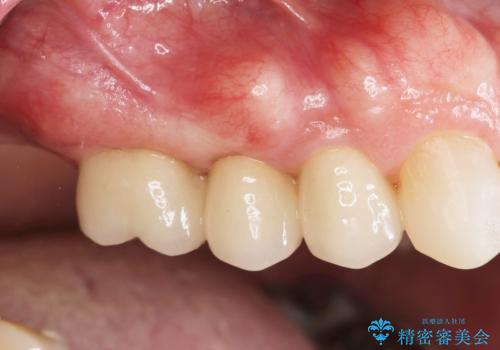

- 39.6万円(ジルコニアクラウン×3・仮歯×3)費用は治療当時の料金となります

審美的かつ、噛みやすい仕上がりに満足いただくことができました。

今後最後方臼歯がないためブリッジに対する力が過大とならないよう噛み合わせの変化を注視する必要があります。